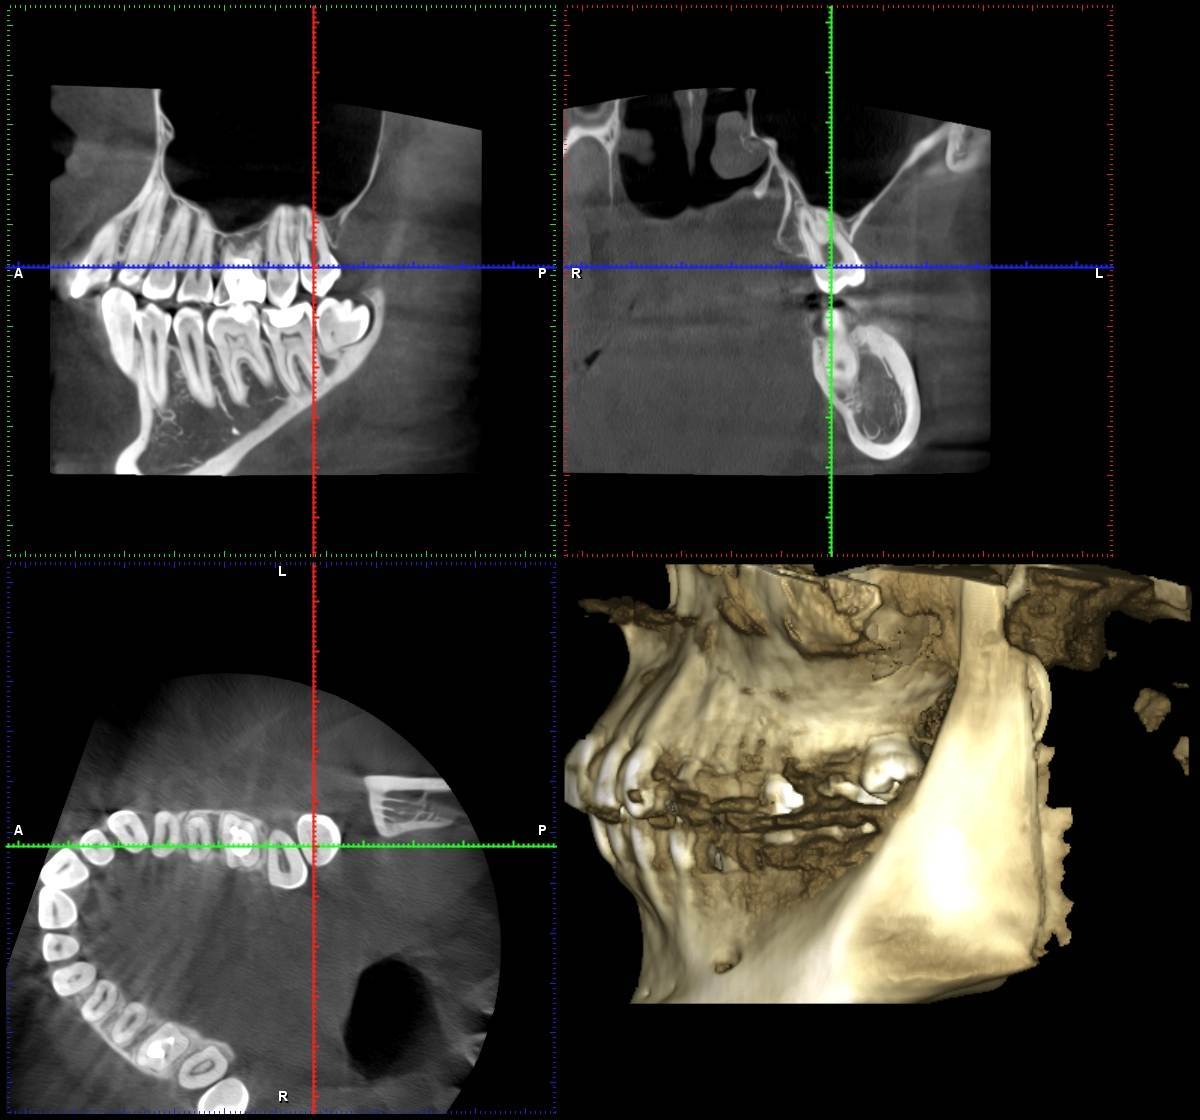

shishok Опубликовано 10 февраля, 2025 Поделиться Опубликовано 10 февраля, 2025 А меня смущает возможное наличие скрытой кариозной полости на передней поверхности 28 зуба. Боль от него может отдавать в соседние зубы.А какой характер боли у Вас? Ссылка на комментарий

shishok Опубликовано 12 февраля, 2025 Поделиться Опубликовано 12 февраля, 2025 21 час назад, Дарья21 сказал: Боль ноющая, очень чувствительна на горячее/холодное и болит очень глубоко, иногда кажется, что в голову отдает 26 зуб так болеть не должен. Проверьте всё же 28. Ссылка на комментарий

wladdX Опубликовано 25 февраля, 2025 Поделиться Опубликовано 25 февраля, 2025 Коллеги, может есть ещё один к\канал в медиальном щёчном корне? Ссылка на комментарий

Carioznik Опубликовано 26 февраля, 2025 Поделиться Опубликовано 26 февраля, 2025 21 час назад, wladdX сказал: Коллеги, может есть ещё один к\канал в медиальном щёчном корне? Есть, мб2- пропущен 1 Ссылка на комментарий

Carioznik Опубликовано 26 февраля, 2025 Поделиться Опубликовано 26 февраля, 2025 (изменено) В 09.02.2025 в 06:00, Дарья21 сказал: Подскажите пожалуйста, что это может быть Исходя из КТ - у Вас есть один необработанный канал, т.е от туда "недоудален нерв"- скорее всего, в этом и причина. Вам лечили зуб используя оптику (увеличительные очки или микроскоп)? Изменено 26 февраля, 2025 пользователем Carioznik 1 Ссылка на комментарий

wladdX Опубликовано 27 февраля, 2025 Поделиться Опубликовано 27 февраля, 2025 (изменено) На КТ кариеса зуба 28 я не увидел. То что можно принять за кариозную полость на фото с экрана компьютера - полость зуба. Зуб имеет наклон в щёчном направлении около 30-40 градусов. Формирование корней у него завершено, так что дальнейшее его прорезывание маловероятно, скорее всего он останется в таком положении. Изменено 27 февраля, 2025 пользователем wladdX Ссылка на комментарий